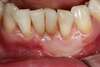

Cas n°1

Dans le cas où on est en présence d'une récession gingivale et que celle-ci continue de progresser soit par la maladie parodontale soit par un brossage traumatique ou que le sensibilité thermique est importante et gênante, on peut greffer de la gencive et maintenir un environnement propice à l'hygiène.